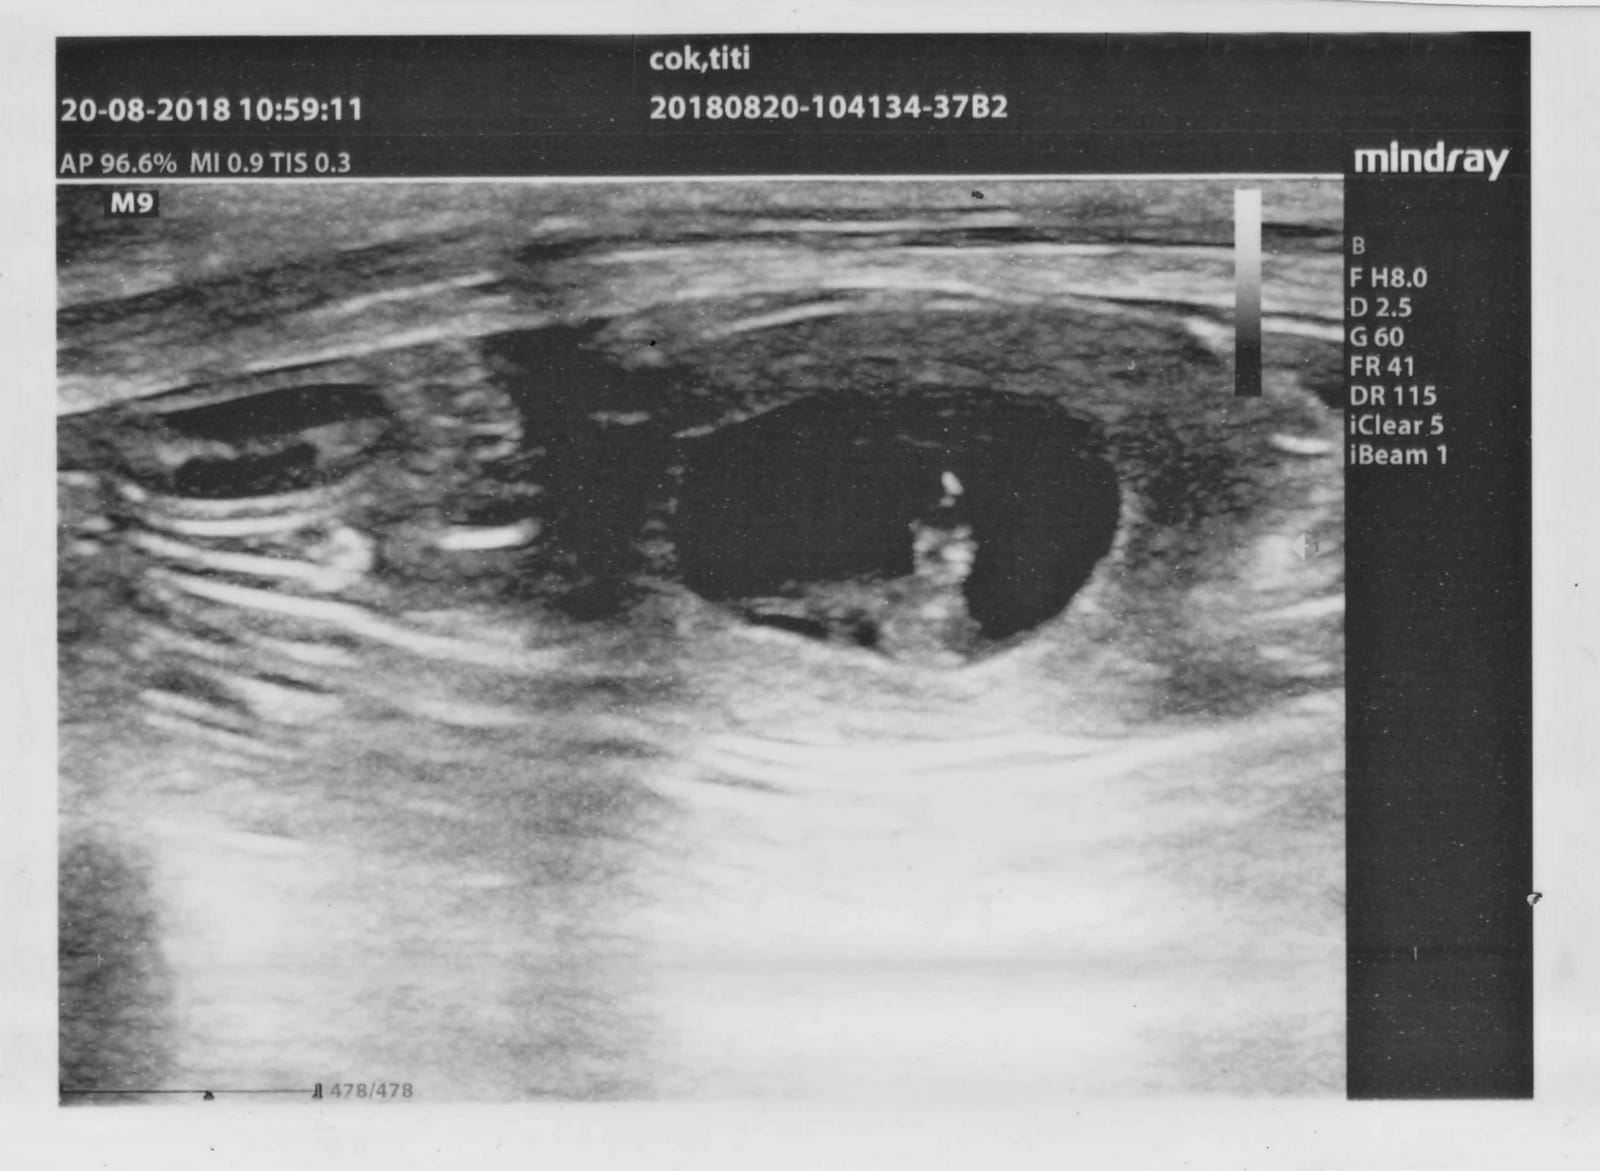

Titi na ultrazvoku ♡ / Titi on ultrasound ♡

Sedaj je tudi uradno 🙂 …. Titi je bila na UZ in prepričali smo se in videli smo, da pričakuje mladičke ♡

It’s official 🙂 … Titi is pregnant ♡